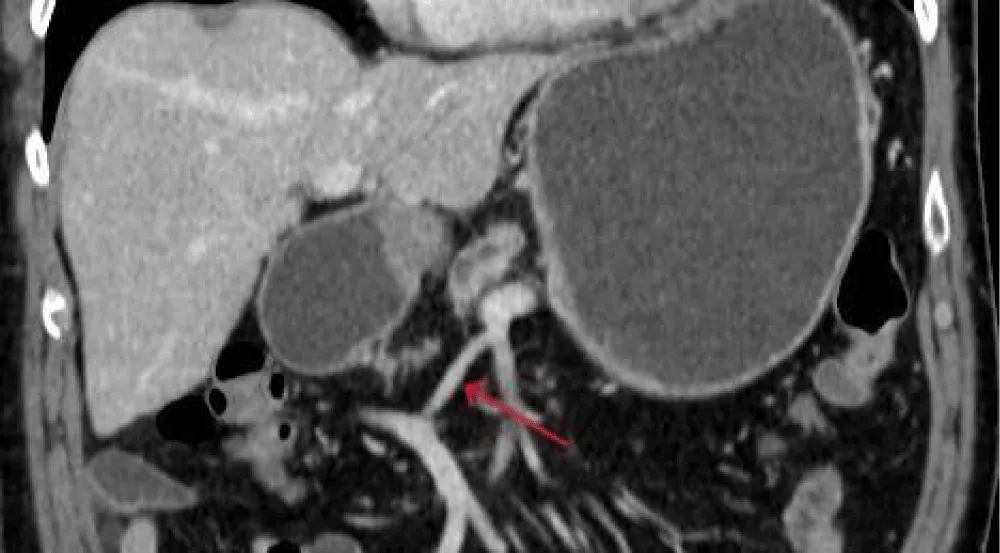

3. Both portal veins are connected extrahepatically via a 3 cm anastomotic vein (Figure 4).

Figure 4: CT scan presenting the extrahepatic interportal anastomotic vein.

Intraoperative findings confirmed the major vascular abnormalities: After Kocher’s manoeuvre, the lesser sac was opened. In contrast to the regular surgical approach, as a next step, the accessory portal vein had to be dissected. Starting from ligamentum teres hepatis, proceeding along the upper margin of the pancreas, and finishing in the mesenteric root. Using the knowledge of anatomy from the CT scan, no surgical complication occurred during this extra step. Now the superior mesenteric artery was dissected and showed no infiltration of the tumor. The ligamentum hepatoduodenale with the small portal vein and the ductus hepatocholedochus were dissected, as well as the accessory left hepatic artery. After cholecystectomy, the right gastric and the gastroduodenal artery were transected. The jejunum was cut 40 centimetres after Treitz. The pancreas was transected, preserving the regular portal vein, the accessory portal vein, and the superior mesenteric artery. After transection of the stomach, reconstruction was performed regularly, and the Whipple procedure was completed. Situs after resection is shown in Figure 5.

Figure 5: Situs after resection; 1 regular portal vein; 2 accessory portal vein; 3 extrahepatic anastomotic vein.